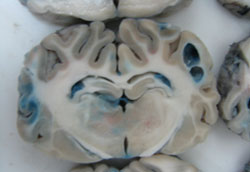

Bisected pig brains laid out side by side, mostly grey with some blue dyed areas throughout

Photo by Miguel Marzal/

Universidad Cayetano Heredia

Peruvian scientists have tested antiparasitic drugs

in pigs. The blue dye indicates disruptions in the

blood-brain barrier.